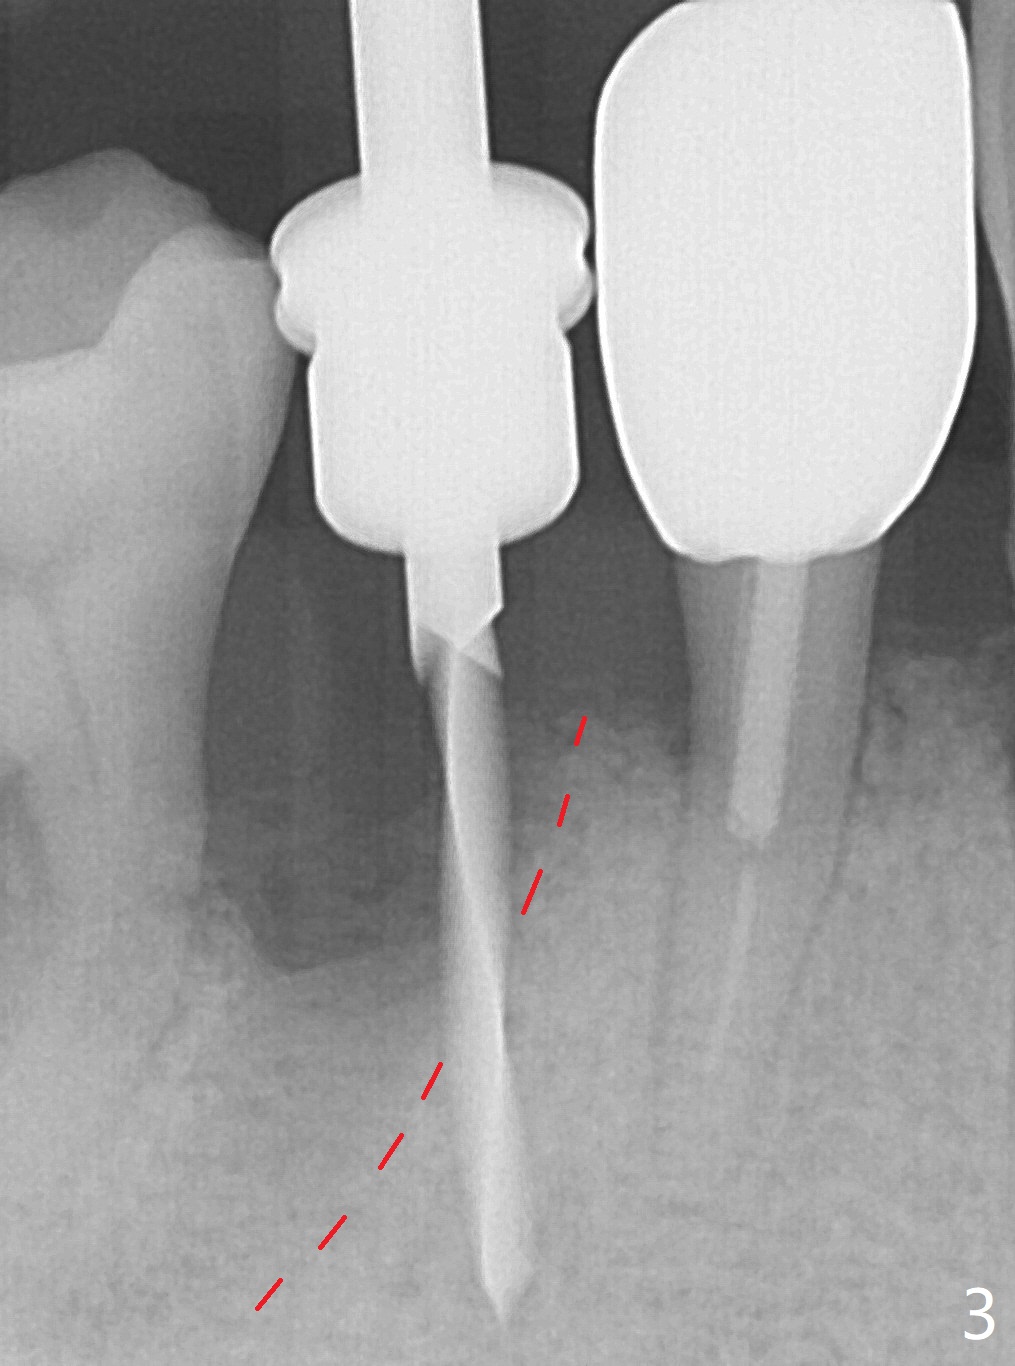

The tooth #29 is easily extracted with granulation tissue attached to the apex (Fig.1,2). The buccal plate is low. Initial osteotomy is established in the mesial slope of the socket for 13 mm subgingival (Fig.3 red dashed line). After adjustment of the osteotomy position and use of Magic Drills 2.8 and 3.3 mm for 15 mm subgingival, a 4x9 mm dummy implant is placed 2 mm subgingival (Fig.4). Final implant (Fig.5: 4x9 mm; red dashed line: socket) is placed 4 mm subgingival (supracrestal buccal; infracrestal lingual); Vanilla graft placed buccodistal (*). With placement of a 4.5x5.7(4) mm abutment (Fig.5), an infraocclusal immediate provisional (Fig.6 P) is fabricated to maintain the interdental papillae. One month later, the abutment dislodges. The patient insists upon no provisional so that he can masticate on the right side, since there is no functional molars on the left side. The implant appears to have osteointegrated 5 months postop (Fig7). The crown is loose 2.5 months post cementation (8.5 months postop); there is bone loss around the implant (Fig.8 *). Vanilla graft is placed after implant removal (Fig.9); in fact the neighboring teeth also have mobility (including periapical radiolucency at #30 (Fig.9 *)).